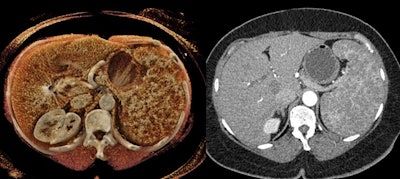

B-cell lymphoma of the spleen on a CT scan (right) and a cinematically rendered CT scan (left). All images courtesy of Dr. Elliot Fishman."Although the potential role of [cinematic rendering] in diagnostic imaging will still require a great deal of study to fully understand, the technique has shown promise in evaluating complex anatomy and pathology involving a number of regions of the body," they wrote (Diagn Interv Imaging, March 28, 2019).

Cinematic rendering of an abdominal CT scan.In the current article, the group discussed three distinct ways in which cinematic rendering could facilitate the evaluation of a variety of conditions affecting the spleen, including the following:

- Vascular conditions: Cinematic rendering is particularly well suited for visualizing vasculature near the hilum of the spleen, an area frequently affected by stomach and pancreatic tumors that restrict blood flow to certain parts of the spleen. Cinematically rendered CT scans display clear demarcations between these infarcted regions and otherwise stable areas.

In addition, the advanced visualization technique clearly depicts textural changes and fluid leakage in the spleen commonly associated with lacerations in trauma patients. These findings may additionally be able to help predict a patient's need for splenectomy.